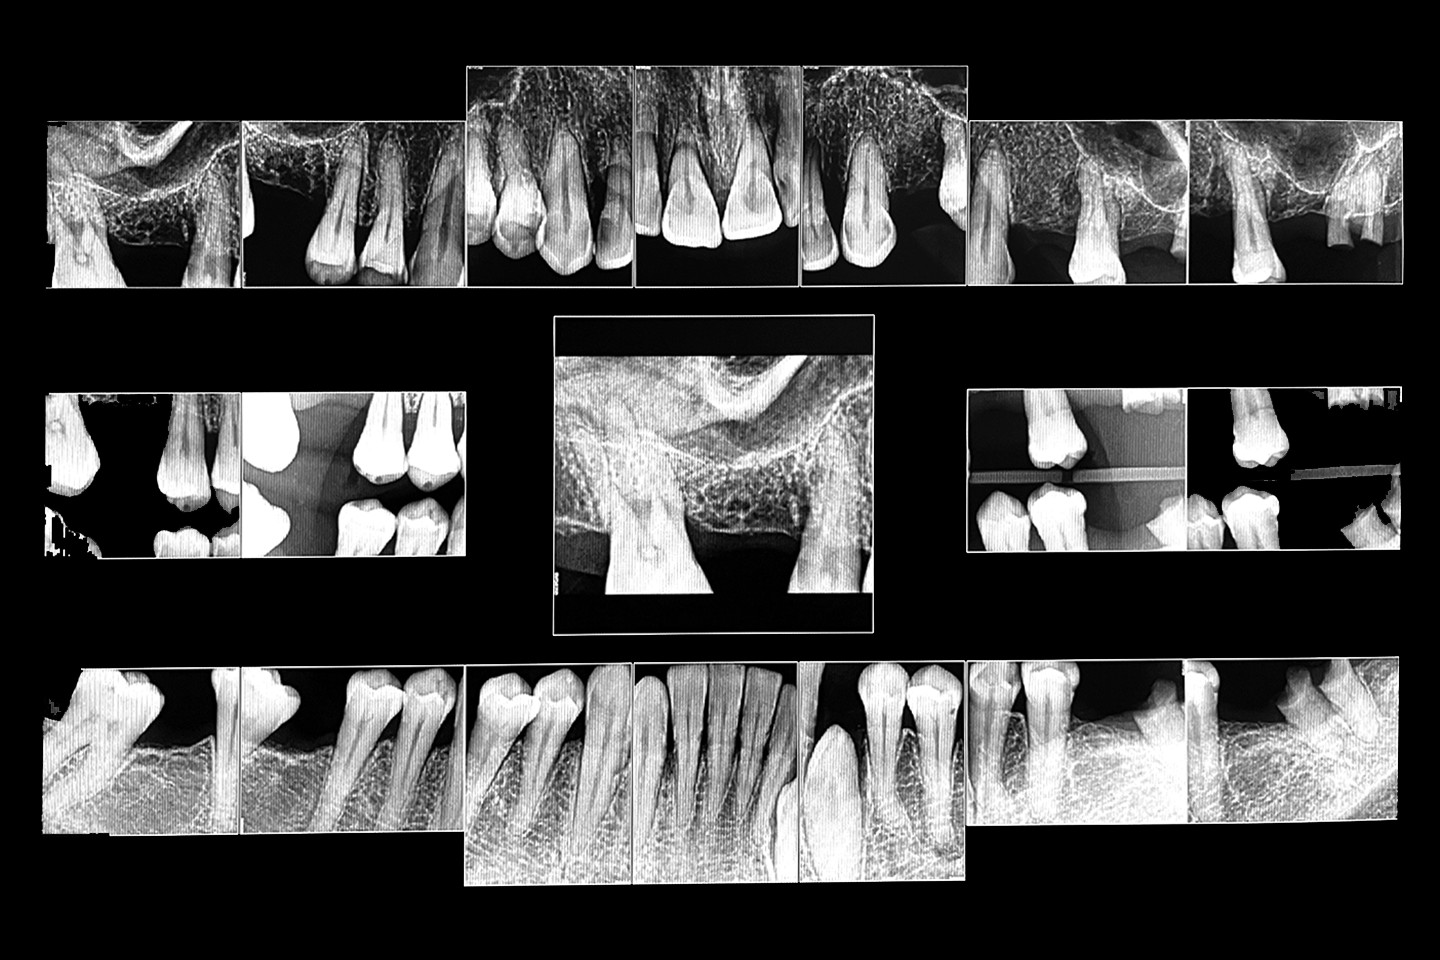

The following case exhibits the features and benefits of utilising Grammetry in combination with innovative screw technology. The 63-year-old male patient with a non-contributory medical history presented with failing dentition in both arches. Diagnostic records were collected, including full-mouth digital radiographs (RVG 6200, Carestream Dental; Fig. 11a), intra-oral scans (Medit i700 wireless; Figs. 11b & c), a large field of view CBCT scan (Carestream 9600; Fig. 11d), and intra-oral and extra-oral photographs (Fig. 11e). The mandible contained an impacted canine as well as several mobile and painful teeth. The maxilla was in a similar condition, having deteriorating, painfully mobile teeth, as well as extensive caries. While the bone loss was significant in the mandible, the vertical dimension of occlusion (VDO) allowed for both arches to be treated with an FP-1 prosthesis.

Fig. 11a: Full-mouth radiograph series revealing caries and periodontal defects.

Based on the assessment of the acquired data, several treatment plans were developed and presented to the patient. Treatment concepts that were considered included salvaging those teeth deemed stable enough to be utilised to retain removable restorations, implant stabilisation with a combination of fixed and removable prostheses, implant-supported overdentures and full-mouth reconstruction with implant therapy. After reviewing the various treatment proposals, the patient selected the last option.